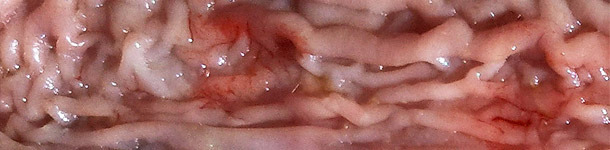

• Engrosamiento de la mucosa en la parte distal del intestino delgado (íleon terminal). Que se presenta rígida y se observa a través de la serosa.

• Ileitis proliferativa en la zona próxima a la válvula ileocecal. Mucosa húmeda con pliegues y muy engrosada.

• Presencia de flecos ligeramente adheridos.

Engrosamiento de la mucosa en parte distal del intestino delgado